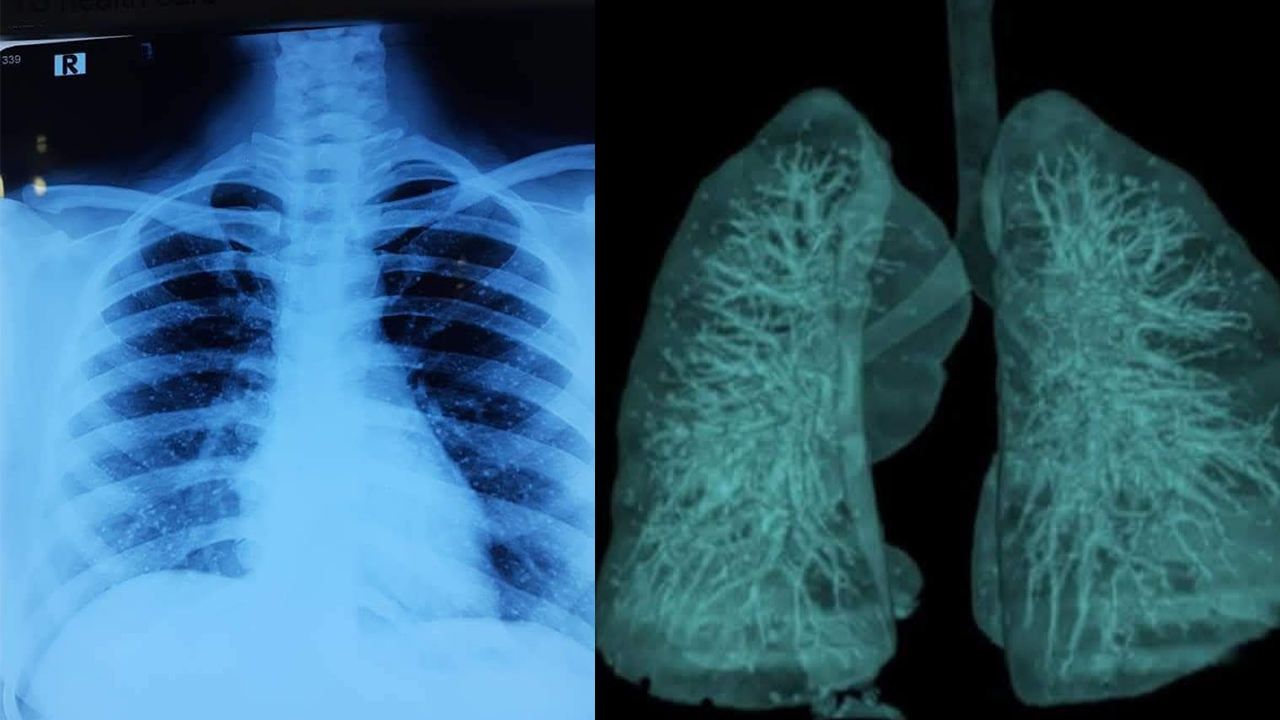

টেস্ট রিপোর্টে ওই নারীর ফুসফুসে দেখা যায় অসংখ্য ক্ষুদ্র পাথরের কণা। মেডিকেলের ভাষায়, পালমোনারি এলভিওলার মাইক্রোলিথিয়াসিস (Alveolar Microlithiasis), সংক্ষেপে পিএএম। এটি এমন একটি বিরল রোগ, যেখানে ফুসফুসের অ্যালভিওলাইয়ের ভেতরে ক্যালসিয়াম ফসফেট জমে ক্ষুদ্র ক্ষুদ্র পাথরসদৃশ গঠন তৈরি করে।

বিশ্বব্যাপী এ রোগের প্রাদুর্ভাব অত্যন্ত কম। প্রতি ১০ লাখ মানুষের মধ্যে মাত্র একজন। এখন পর্যন্ত নথিভুক্ত কেস মাত্র ১৫০০।

ডা. সাঈদ এনাম জানান, পিএএম একটি জেনেটিক্যাল রোগ। অনেক ক্ষেত্রে উপসর্গহীন থাকে। যক্ষ্মা, নিউমোনিয়া বা ফুসফুসের ক্যানসারের মতো মারাত্মক জটিলতাও তৈরি করে না। রোগটি নিয়ে গবেষণা এখনও চলমান। বিশেষজ্ঞদের মতে, সচেতনতা ও প্রাথমিক পরীক্ষা মিলিয়ে এমন বিরল রোগও সময়মতো শনাক্ত করা সম্ভব।